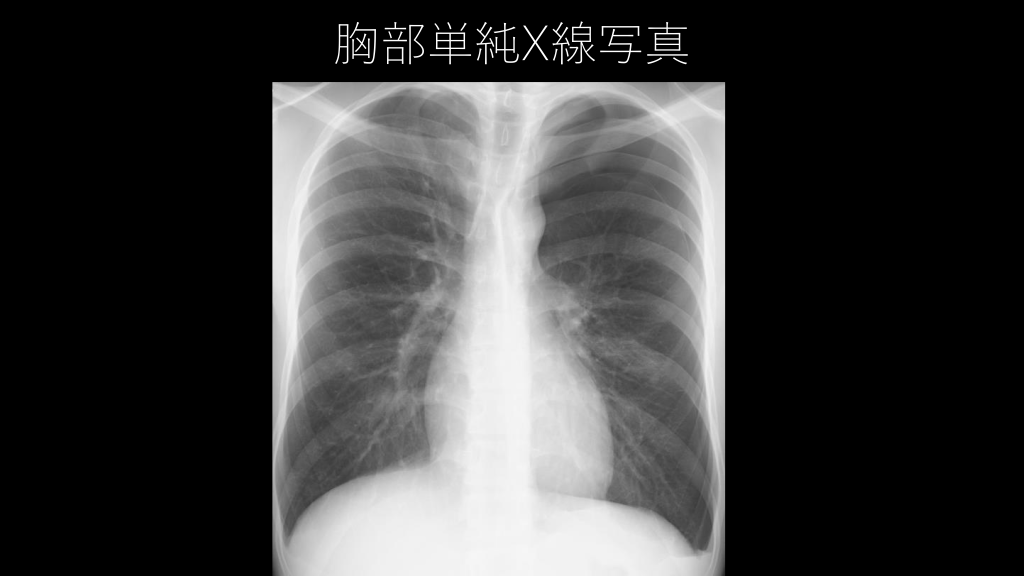

ある日の救急外来 • 呼吸困難を主訴に来院された男性。 • 胸部単純X線写真を施行してみると・・・。

胸部単純X線写真